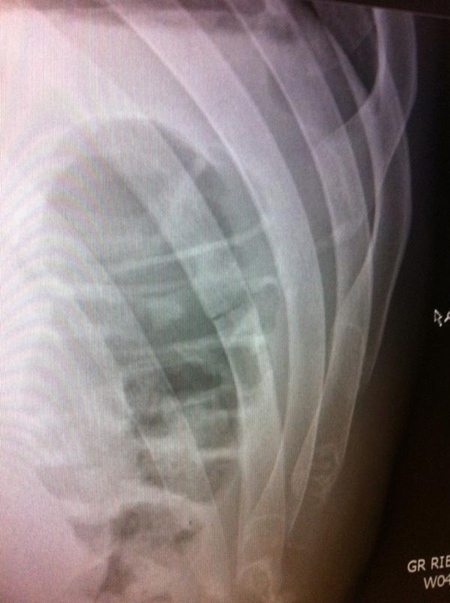

Вчера Юрайя Фабер проиграл Ренану Барао в главном бою турнира UFC 149 и не смог завоевать титул временного чемпиона UFC в легчайшем весе. В результате медицинского обследования, проведенного после турнира выяснилось, что у Фабера было сломано ребро, что хорошо заметно на рентгеновском снимке бойца.

«Поздравляю Ренана Барао. Он жесткий парень. Сильным ударом колена сломал мне ребро в первом раунде. Спасибо всем за поддержку».